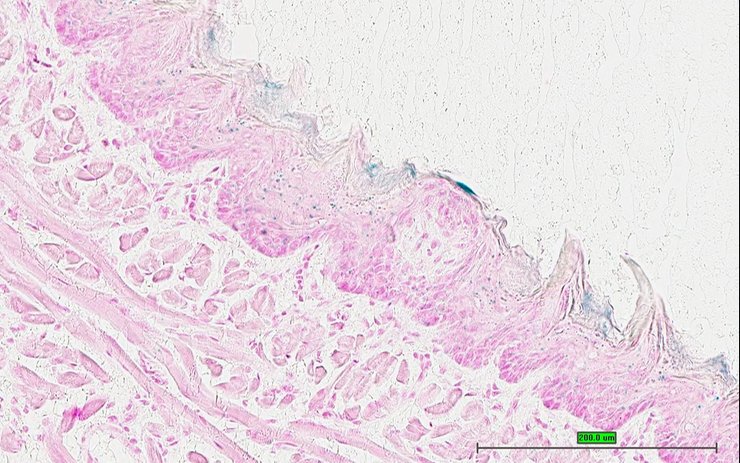

Structure Level Pattern Image Note

TS28: skin Present UC Davis_1886838

Specimen UC Davis_1886839: postnatal adult; Arhgef12tm1b(KOMP)Wtsi/Arhgef12+ (more )

TS28: skin Present UC Davis_1886839

Specimen UC Davis_1886840: postnatal adult; Arhgef12tm1b(KOMP)Wtsi/Arhgef12+ (more )

TS28: skin Present UC Davis_1886840

Specimen UC Davis_1886841: postnatal adult; Arhgef12tm1b(KOMP)Wtsi/Arhgef12+ (more )

TS28: skin Present UC Davis_1886841

Specimen UC Davis_1886842: postnatal adult; Arhgef12tm1b(KOMP)Wtsi/Arhgef12+ (more )

TS28: skin Present UC Davis_1886842

TS28: skin Present UC Davis_1886911

Specimen UC Davis_1886912: postnatal adult; Arhgef12tm1b(KOMP)Wtsi/Arhgef12+ (more )

TS28: skin Present UC Davis_1886912